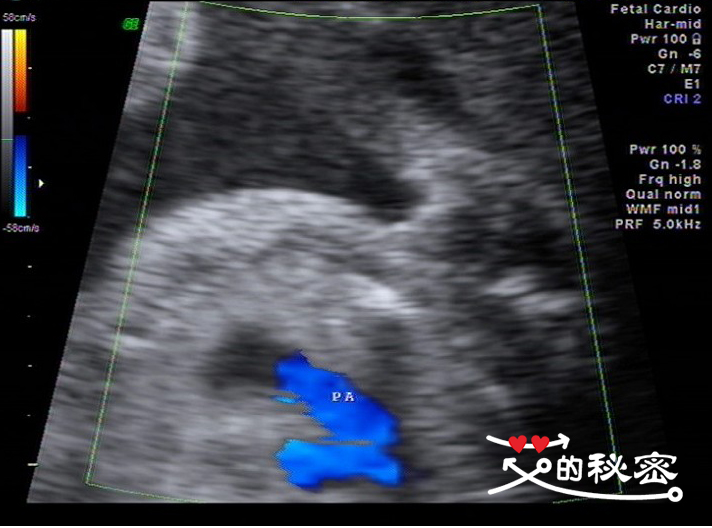

8、胎儿胸部:肺脏可见,心脏位置未见异常,心胸比例正常,心律整,由四腔心观“十”字结构存在,房室大小比例正常,卵圆孔及卵圆孔瓣可显示,左右房室瓣可显示,启闭好。流出道切面见主动脉与左室相连,肺动脉与右室相连。简写英文的意思LV左心室,AO主动脉,RV右心室,PA肺动脉。